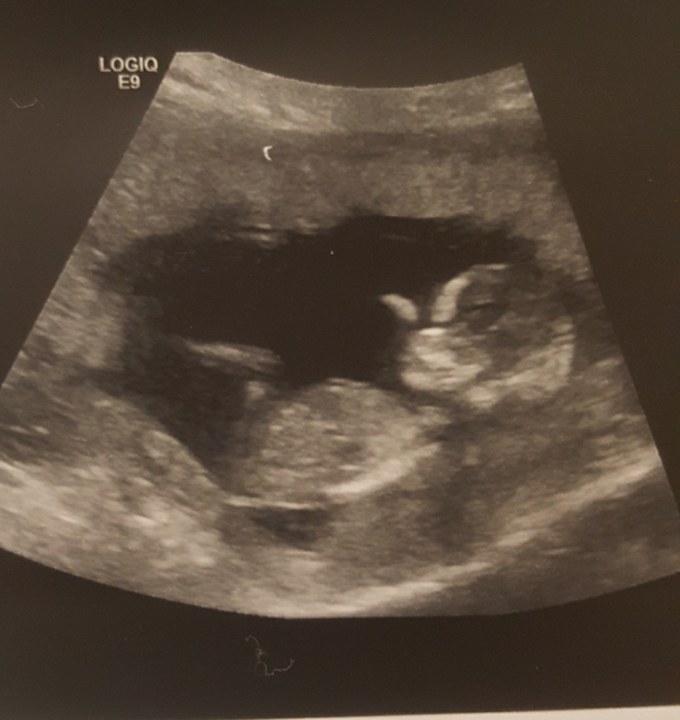

6w: (transvaginal- done at the same office with my son and he was on the opposite side so i'm very curious! I suck at ramzi..)

Attachment 36547